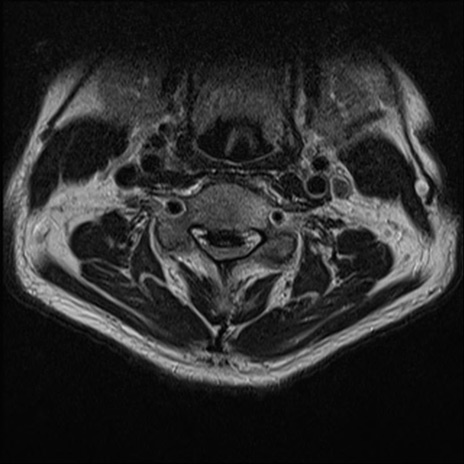

【整形】TIPS症例7 頚椎MRI T2WI(横断像)

頚椎MRI

矢状断像と横断像